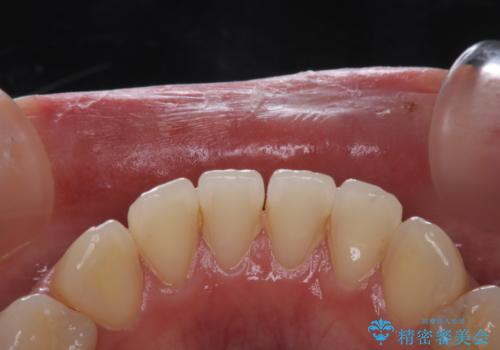

PMTCを行う際には担当の歯科衛生士が、患者様1人1人の虫歯・歯周病などのリスク・ブラッシングスキルなどを確認します。

日々の磨き残しや唾液の成分などによりバイオフィルムや歯石はどうしても付着してしまいます。歯石や汚れを放置していると、そこで病原菌が繁殖す始めます。歯肉に炎症が生じると歯周病などの引き金となります。

そのため、2~3か月に1回は、歯科医院での専門的クリーニングをすることが大切です。